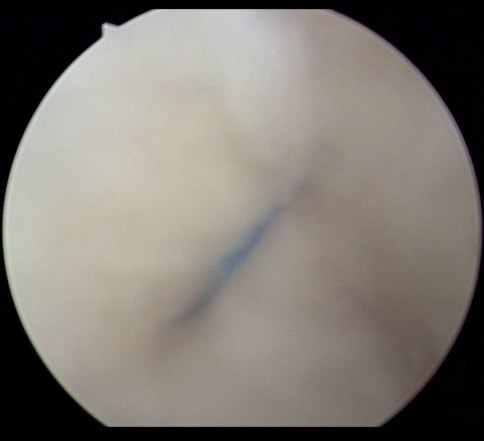

腕关节平扫